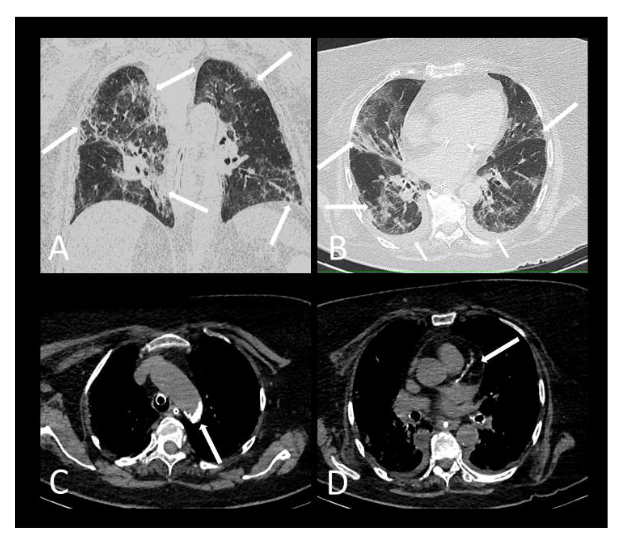

The institution’s radiologists analysed all chest exams, and the qualitative score of pulmonary opacities of COVID-19 patterns (viral pneumonia) was performed independently, classifying the findings into: (a) less than 25%, (b) between 25% and 50% or (c) equal to or greater than 50%. Our study considered only the evaluation of chest CT reports by radiologists at the Institution.

A greater frequency of deaths was found in males compared to females without statistical significance. However, the patients who died (Figure 2 and 3) with statistical significance were older and more frequently presented systemic arterial hypertension, diabetes mellitus, chronic kidney failure, dyspnoea, more than 50% extension pulmonary involvement and moderate-severe CACs or coronary arterial stent.

In this retrospective study, by using chest CT scans performed for evaluation of COVID-19 lung complication, a simple visual overall assessment of CACs scoring could be generated for risk assessment of death. We observed an association between the group denominated with presence of CACs (moderate and severe CACs and stent) and patient lethality. Patients who died due to COVID-19 were older and more frequently presented with systemic arterial hypertension, diabetes mellitus, chronic renal failure, dyspnoea and more than 50% extensive lung involvement on chest CT.